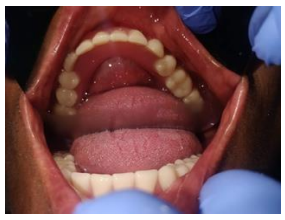

A 49 years old female patient reported to the department of prosthodontics with multiple missing teeth and sunken cheeks. Intra oral examination revealed that the mandibular was completely edentulous and the maxillary arch had three upper right posterior teeth. The patient had moderately resorbed maxillary and severely resorbed mandibular edentulous ridges. The patient was conscious about her sunken cheeks and desired a prosthesis that would make her face look fuller and healthier.

Treatment plan was formulated, keeping the patient’s demand in mind. It was decided to give the patient mandibular complete denture and maxillary dentures with magnet retained cheek plumpers.